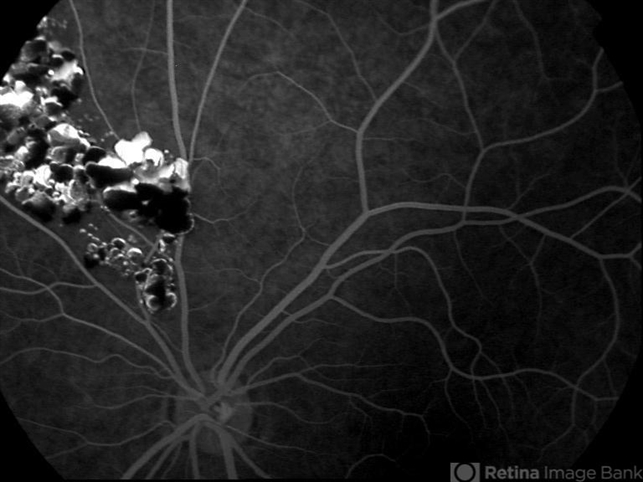

- Cavernous hemangioma of the retina and CNS

- cavernous hemangioma of the retina

- Fluorescein angiogram of an 8 year-old boy with a cavernous hemangioma of the retina.